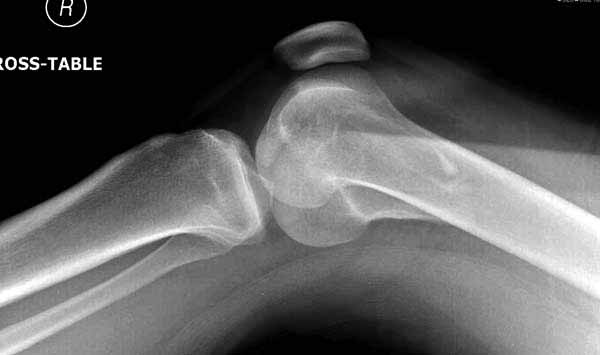

Представленный снимок не дает полную информацию. Там вроде простой перелом, но на самом деле, кроме смещенного (латерального, возможно медиального?) мыщелка на второй проекции имеется медиальный короткий дистальный фрагмент в флексии. Надо было сделать прямой снимок с захватом малоберцовой, который ориентировал бы стороны. Без КТ обычный снимок в дистракции поможет разобраться в топографии фрагментов.

Во время фиксации надо соблюдать осторожность, особенно с коротким фрагментом на другой стороне. Обычно на прямой проекции трудно заметить флексионную деформацию мыщелка и упускается адекватная фиксация. Без пластины винты не смогут удержать, и мыщелок на второй стороне может сместиться. Для фиксации надо развернуть мыщелок и удержать винтами. Качество межмыщелковой репозиции надо проконтролировать артротомией. Из всех доступов только передне-латеральный доступ (Swashbuckler) даст обзор для ревизии качества фиксации, который в будущем может быть использован для артропластики.

Кстати, из вашего снимка, если отмечены вашим рентгенологом правильно, тогда получается снимок левого колена, и, соответственно, длинный переходящий в диафиз мыщелковый фрагмент находится медиально. Если так, тогда меняется сценарий фиксации!!!

И не обратите, коллега, пока не сделаете четкие анфасные снимки (лучше с дистракцией) где будет четко визуализироваться малоберцовая кость. Думается, что и КТ здесь будет уместно, дабы не пропустить возможное флексионное повреждение (перелом Hoffa).